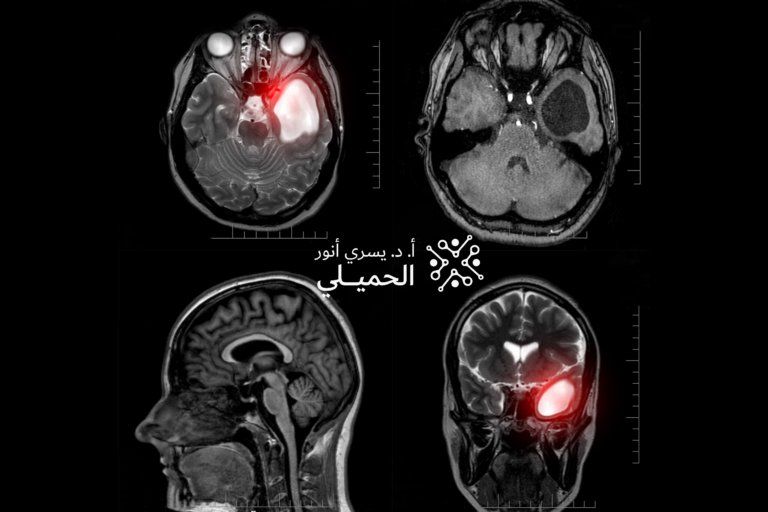

3. التصوير بالرنين المغناطيسي MRI

وهو أدق وسيلة لتحديد:

-

حجم الورم

موقعه

تأثيره على العصب البصري

وقد يُستخدم الـ CT في بعض الحالات.